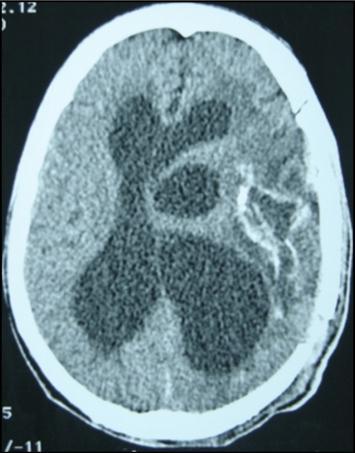

A 27 years-old male patient was admitted with 1 month history of headache, fever, short term memory lack, aphasia, right hemiparesis and seizures. He had liver hydatid cysts excised 8 years before and was treated with adjuvant medication (albendazole). The neurological examination revealed right central third cranial nerve palsy and hemi paresis, with Babinski sign positive, aphasia and papilledema on ocular fundus. The Glasgow Coma Scale was evaluated to 10/15 (E:3; V:1; M:6). A brain CT scan showed a large left temporoparietal intracerebral multiple and calcified hydatid cysts, important mass effect with midline shift about 7 mm following by an obstructive hydrocephalus (Figure 1). Other cysts were found in thalamic region (Figure 2). The Thoraco-abdominal CT scan showed multiple intra peritoneal hydatid cysts (Figure 3). A left temporo parietal craniotomy was performed in emergency. After corticectomy, using Arana-Iniguez technique, the appearance of the capsule suggested infected hydatid cysts with a purulent material which was aspirated. Numerous hydatid cysts were lifted away and several daughter vesicles were carefully removed without rupture (Figure 4). Macroscopically, the abscess wall appeared to be thick, calcified and tightly attached to lateral ventricular, so it could not be removed. The deep cyst overlying the third ventricle was left.in place. Microscopic examination demonstrated live scoleces, protoscoleces and multiple hooks. These findings are consistent with hydatid cyst (granulosis ecchinococcus) (Figure 5). Bacteriology examination found several white blood cells in the pus (neutrophilia) and infection by streptococcus pneumonia. This was consistent with infection. After surgery, the patient had medication (albendazole, specific antibiotherapy and phenobarbital). The inflammation assessment in the blood showed leukocytosis, a high C-reactive protein rate and increased erythrocyte sedimentation rate. Post operative CT scan was performed and showed the residual calcified capsule and decreased ventricular size (Figure 6). Clinical improvement was achieved after treatment. One month after the initial diagnosis, CT scan of the brain showed no recurrence and a physical examination revealed a neurologically intact, fully functional patient and eyes fundus normal. He was discharged and went to abdominal surgery two months later with complete intra abdominal cysts removal. Albendazole treatment was continuing for six months and radiological exploration was performed by brain MRI with spectroscopy at three and six month later. This showed that infection had resolved and the deep cyst overlying the third ventricle is less spherical (Figure 7, Figure 8). Four years later, the outcome was good.

Figure 1.axial CT scans of brain showing multiple hydatid cysts (A) with calcified capsule (B).